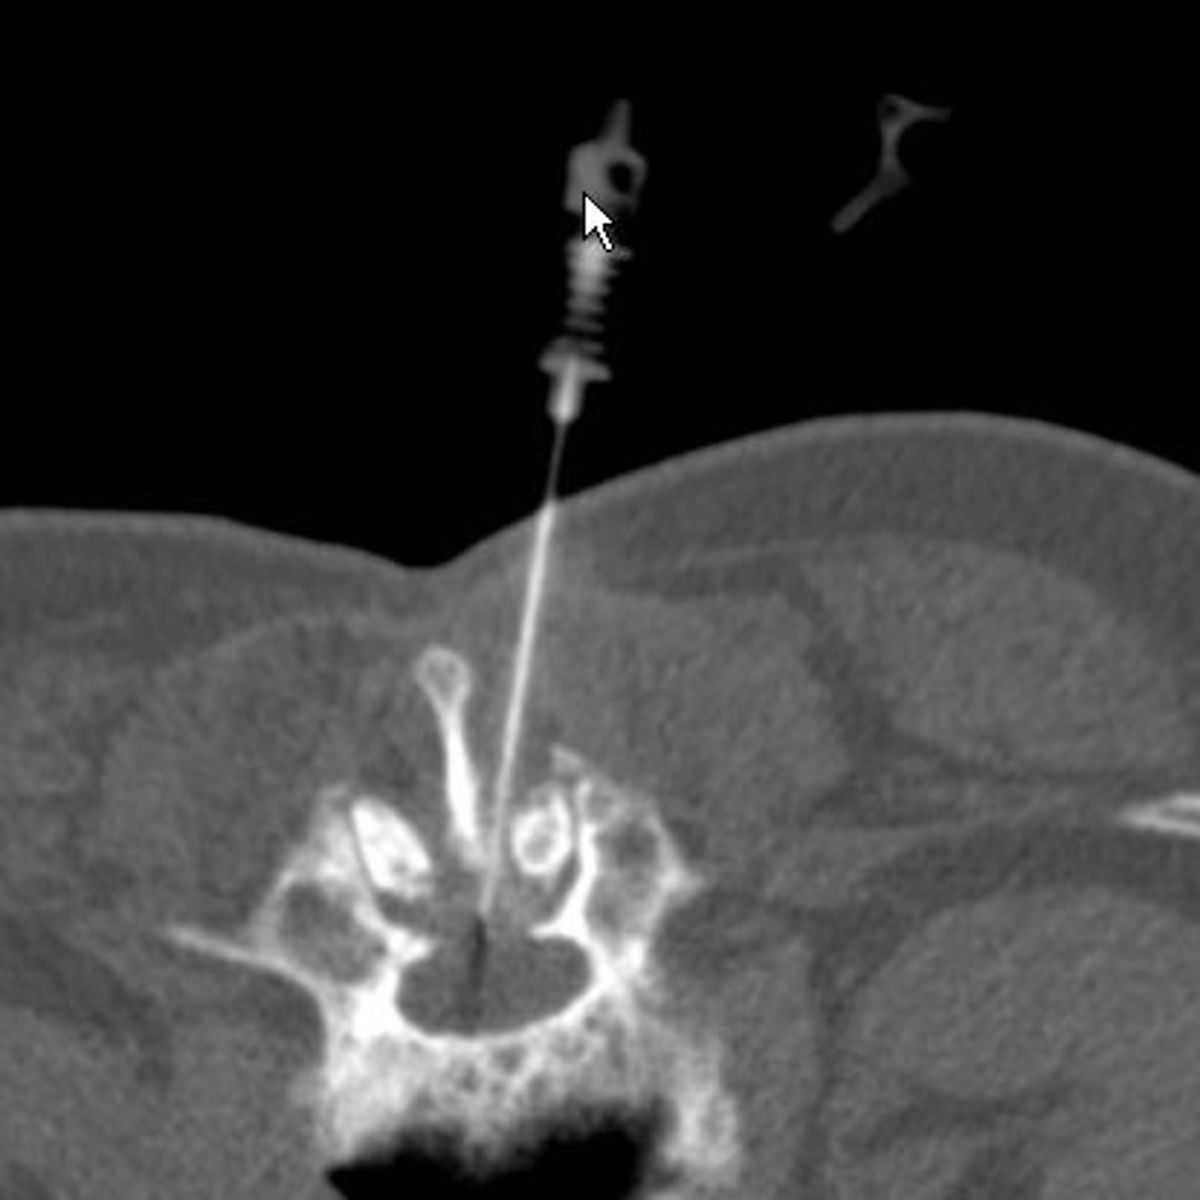

Zur Therapie stehen unsere modernen Großgeräte wie Computertomographen und Durchleuchtungsgeräte (Zwei-Ebenen-Angiographie) zur Verfügung, die schonendes und präzises Arbeiten im Millimeterbereich gewährleisten, was der Sicherheit und der Verbesserung der klinischen Ergebnisse für unsere PatientInnen dient.

- Minimalinvasive CT-gesteuerte Schmerztherapien

- ISG-Infiltrationen/-denervierungen